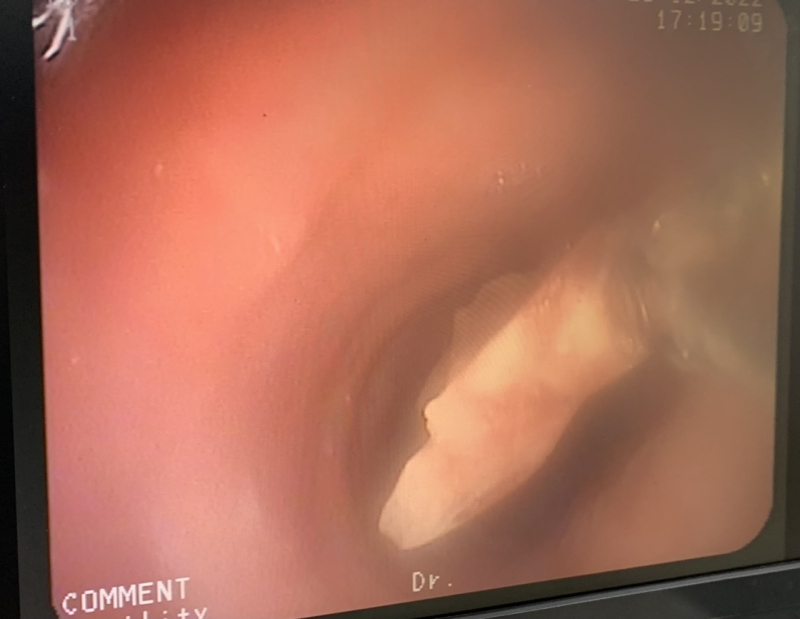

Quá trình nội soi phế quản ống mềm phát hiện dị vật góc cạnh dài 1,5 cm là mảnh xương gây bít tắc ở thùy dưới phổi phải gây tổn thương viêm mủ. Ekip nội soi can thiệp Khoa Hô hấp, Bệnh viện Bãi Cháy đã tiến hành gắp dị vật, hút rửa sạch phế quản thùy dưới phổi phải. Sau can thiệp 24h, bệnh nhân tỉnh, phổi thông khí tốt, giảm ho, không còn sốt, sức khỏe ổn định, tiếp tục được điều trị kháng sinh, kháng viêm.

Can thiệp nội soi phế quản gắp dị vật đường thở cho người bệnh tại Bệnh viện Bãi Cháy

Dị vật là mảnh xương được lấy ra qua can thiệp nội soi phế quản ống mềm tại Bệnh viện Bãi Cháy